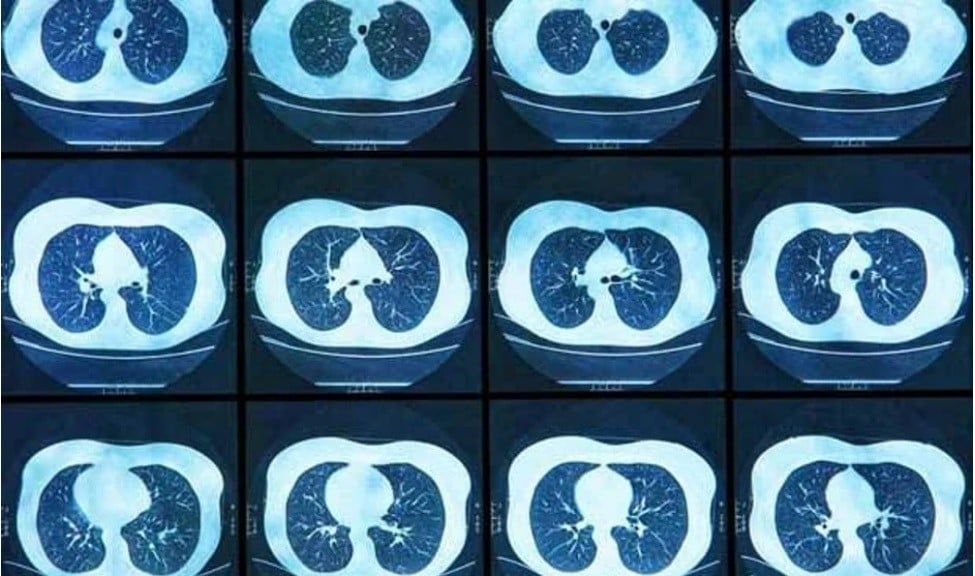

España sigue sin contar con un cribado de cáncer de pulmón poblacional consolidado, y proyectos como Cassandra buscan ofrecer una solución para incluir esta detección precoz en la cartera de servicios del Sistema Nacional de Salud (SNS). Según ha podido saber Redacción Médica, los principales impulsores del proyecto se han reunido recientemente con los técnicos del Ministerio de Sanidad. Ante la opción de homogeneizar el cribado para evitar que sea oportunista, junto con otros avances realizados hasta la fecha, Sanidad los ha visto “con buenos ojos”, y ahora mismo se espera conocer una valoración definitiva para conocer si Cassandra acabará reforzando un futuro documento en relación al cribado en este tipo de cáncer en España...